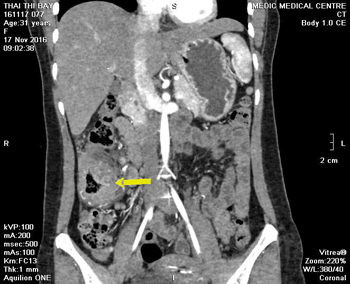

Trong lần tái khám 2 tuần tiếp theo sau đó, xét nghiệm máu bạch cầu ái toan trở về bình thường (2,5%), men gan AST và ALT trong giới hạn bình thường, chỉ có GGT còn tăng 160 IU/L, chụp lại MSCT bụng để kiểm tra diễn tiến tổn thương ở gan và đại tràng. Trên hình ảnh MSCT cho thấy tổn thương gan thay đổi ít so với lần chụp trước (đến thời điểm này mới 1 tháng kể từ khi dùng thuốc). Tuy nhiên, tổn thương ở đại tràng ngang diễn tiến rất tốt, thành chỉ còn 8mm (so với 20mm trong lần chụp trước) (Hình 5).

Hình 5a. Áp xe nhu mô gan (P) chưa thay đổi nhiều (sau 4 tuần) và Hình 5b. Tổn thương thành đại tràng ngang đã giảm rõ rệt trong lần tái khám